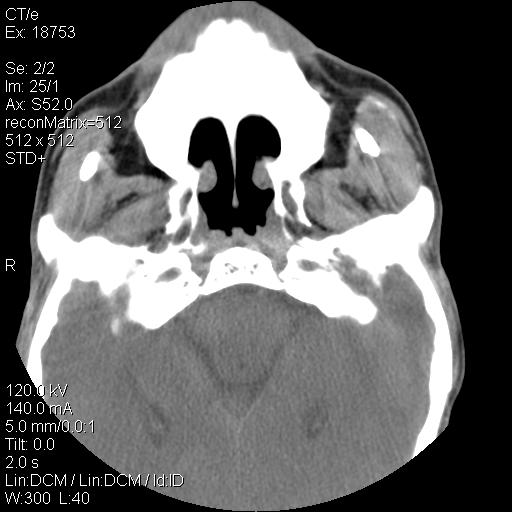

标题: CT21693:男 58岁 右侧咽部疼她2天余 PE:右侧扁桃体肿大 压痛 [打印本页]

标题: CT21693:男 58岁 右侧咽部疼她2天余 PE:右侧扁桃体肿大 压痛

右化脓性扁桃体炎症伴咽后壁脓肿形成.

喉部新生物,喉癌可能大,建议喉镜取组织活检。

结合病史,考虑感染性病变;建议抗炎治疗复查排除肿瘤性病变。